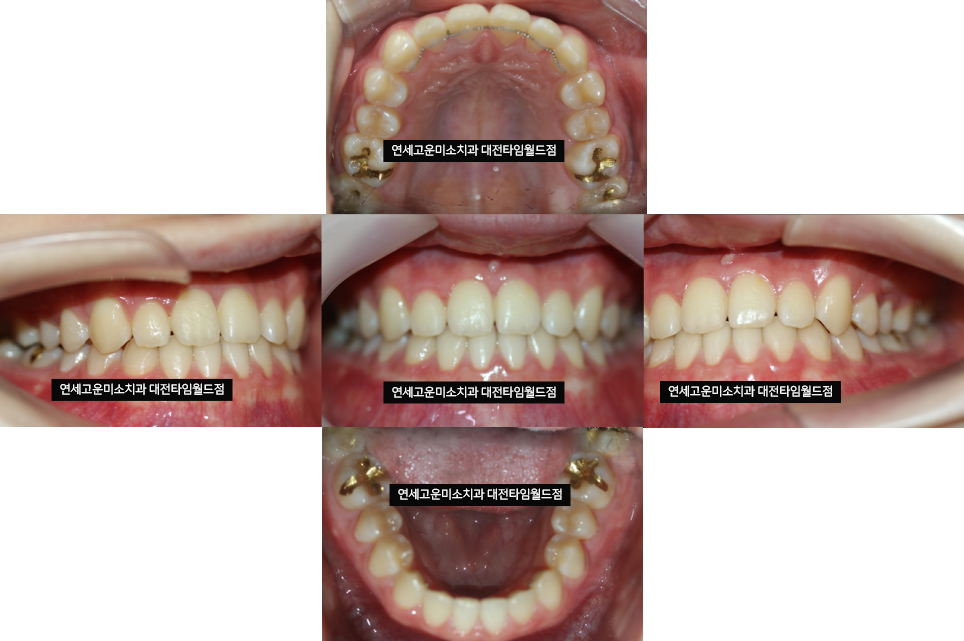

양악 수술 없이 교정 후 모습입니다

턱이 살짝 들어가 보입니다

그것은 꽉 문 상태가 아닌

앞니끼리 맞문 상태로 교합이

형성되었기 때문에 턱이 들어간 것처럼

보이게 됩니다.

(실제로 턱이 짧아지는 것은 아닙니다)

교정 후 입안 모습입니다

반대교합도 깔끔하게 해결되고

교합도 훌륭합니다.

치료 전후 비교 모습입니다

배열도 가지런해지고

오른쪽 위에 들어가 있던 작은 어금니도

배열이 되어서 기능을 할 수 있게

만들어주었습니다.